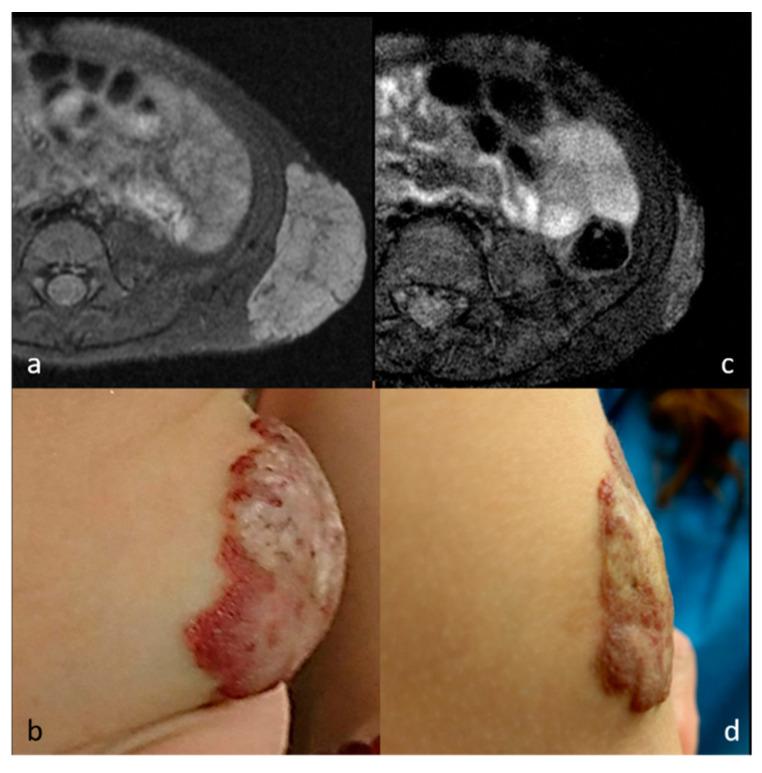

: To evaluate the effectiveness of radiofrequency ablation (RFA) using the moving-shot technique for benign soft tissue neoplasm. : This retrospective study reviewed eight patients with benign soft tissue neoplasm presenting with cosmetic concerns and/or symptomatic issues who refused surgery. Six patients had vascular malformation, including four with venous malformation and two with congenital hemangioma. The other two patients had neurofibroma. All patients underwent RFA using the moving-shot technique. Imaging and clinical follow-up were performed in all patients. Follow-up image modalities included ultrasound (US), computed tomography (CT), and magnetic resonance (MR) imaging. The volume reduction ratio (VRR), cosmetic scale (CS), and complications were evaluated. : Among the seven patients having received single-stage RFA, there were significant volume reductions between baseline (33.3 ± 21.2 cm), midterm follow-up (5.1 ± 3.8 cm, = 0.020), and final follow-up (3.6 ± 1.4 cm, = 0.022) volumes. The VRR was 84.5 ± 9.2% at final follow-up. There were also significant improvements in the CS (from 3.71 to 1.57, = 0.017). The remaining patient, in the process of a scheduled two-stage RFA, had a 33.8% VRR after the first RFA. The overall VRR among the eight patients was 77.5%. No complications or re-growth of the targeted lesions were noted during the follow-up period. Of the eight patients, two received RFA under local anesthesia, while the other six patients were under general anesthesia. : RFA using the moving-shot technique is an effective, safe, and minimally invasive treatment for benign soft tissue neoplasms, achieving mass volume reduction within 6 months and significant esthetic improvement, either with local anesthesia or with general anesthesia under certain conditions.

这项回顾性研究纳入了 8 名因美容需求和/或症状而拒绝手术的良性软组织肿瘤患者。6 名患者为血管畸形,包括 4 例静脉畸形和 2 例先天性血管瘤。另外 2 例患者为神经纤维瘤。所有患者均采用移动射击技术行 RFA。所有患者均进行了影像学和临床随访。随访的影像学方式包括超声(US)、计算机断层扫描(CT)和磁共振成像(MR)。评估了体积减少率(VRR)、美容评分(CS)和并发症。

在接受单阶段 RFA 的 7 名患者中,基线(33.3±21.2cm)、中期随访(5.1±3.8cm,P=0.020)和最终随访(3.6±1.4cm,P=0.022)的体积均有显著减少。最终随访时的 VRR 为 84.5±9.2%。CS 也有显著改善(从 3.71 降至 1.57,P=0.017)。正在接受预定两阶段 RFA 的 1 名患者,在第一次 RFA 后 VRR 为 33.8%。8 名患者的总体 VRR 为 77.5%。在随访期间,未发现靶向病变有并发症或复发。8 名患者中,2 名在局部麻醉下接受 RFA,其余 6 名在全身麻醉下接受 RFA。